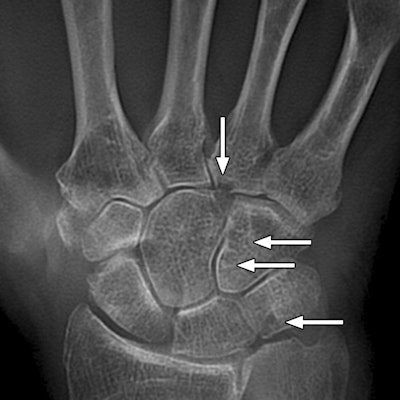

Images are of a 67-year-old man with rheumatoid arthritis. Bone erosion with significant overlapping of bones (arrows) can be difficult to evaluate on radiography (above), compared with tomosynthesis (below and bottom). Images courtesy of AJR.